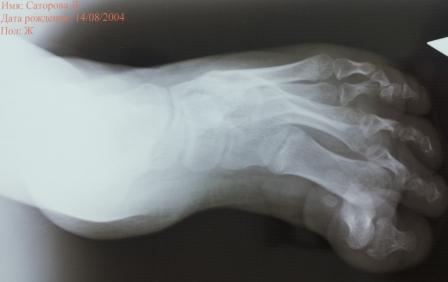

Уважаемые коллеги, специалисты подиатрии! Сегодня обратилась девочка

2004 г.р. , лет 7-8 назад оперирована в одной центральной клинике,

по-видимому, по поводу косолапости, ахиллопластика и аппаратом

Илизарова( документов нет).

Просит исправить деформацию и чтобы могла одеть нормальную обувь .Фото и

Р-графия предлагается, где имеется вывих в плюснефаланговом суставе и

медиальная девиация всех пальцев, 1- палец пассивно поднимается до

горизонтали, при этом подошвенная фасция сильно натягивается, но

разгибания нет, медиальная девиация пальцев исправлению поддается без труда.